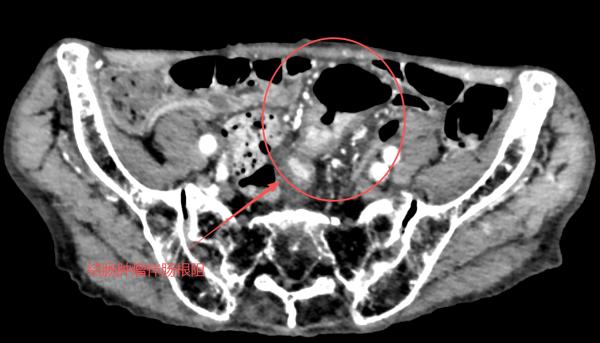

时间倒回至3个月前。章爷爷突然出现腹痛症状,排便习惯也变得异常——每天4-5次,仅能排出少量粘液状大便。谁料症状越来越重,半个月前,他更是彻底陷入了“便秘困境”,连一点大便都解不出来。家人心急如焚,迅速将他送入鄞州区第二医院(宁波市中西医结合医院)消化内科。肠镜检查的结果如同一记重锤:乙状结肠癌伴完全性肠梗阻,肿瘤如一块巨石,堵死了整个肠腔,内镜根本无法通过。